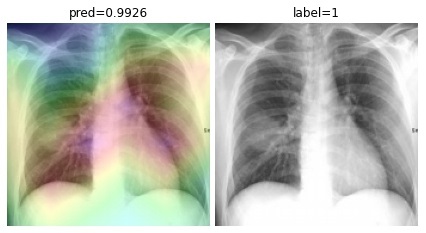

5.3 COVID-CXNet

To overcome the aforementioned issues and force the model’s attention to the correct regions of interest (ROIs), we introduce the COVID-CXNet. Our model is initialized with the pretrained weights from CheXNet. A dataset of 3,628 images, 3,200 normal CXRs and 428 COVID-19 CXRs, are divided into 80% as training-set and 20% as test-set. Batch size is set to 16, rather than 32 in previous models, regarding memory constraints. Grad-CAMs of the COVID-CXNet for random images are plotted in Fig. 15.

Refer to caption

Figure 15: Grad-CAM visualization of the proposed model over sample cases

More Grad-CAMs are available in Appendix A. Heatmaps are more accurate than previous models, while an accuracy of 99.04% and an f-score of 0.96 are achieved. Table 3 is the confusion matrix of the proposed model.

Proposed CheXNet-based model is capable of correctly classifying images. In many cases, it can localize pneumonia findings more precisely than the CheXNet. An example is illustrated in Fig. 16.

(a)

(b)

(c)

Figure 16: Comparison between the CheXNet and the proposed model; (a) is the image with patchy opacities in the upper left zone, (b) and (c) are heatmaps of the CheXNet and the proposed COVID-CXNet, respectively.

Fig. 16 shows a CXR with an infiltrate in the upper lobe of the left hemithorax [47]; while CheXNet missed the region of pneumonia, the proposed model correctly uncovered the infiltration area. One concern about COVID-CXNet results is that it has pointed into other irrelevant regions, even outside the lungs. The same problem happens when there are frequently-appeared texts and signs, such as dates, present in the image. Fig. 17 shows how text removal can improve model efficiency.